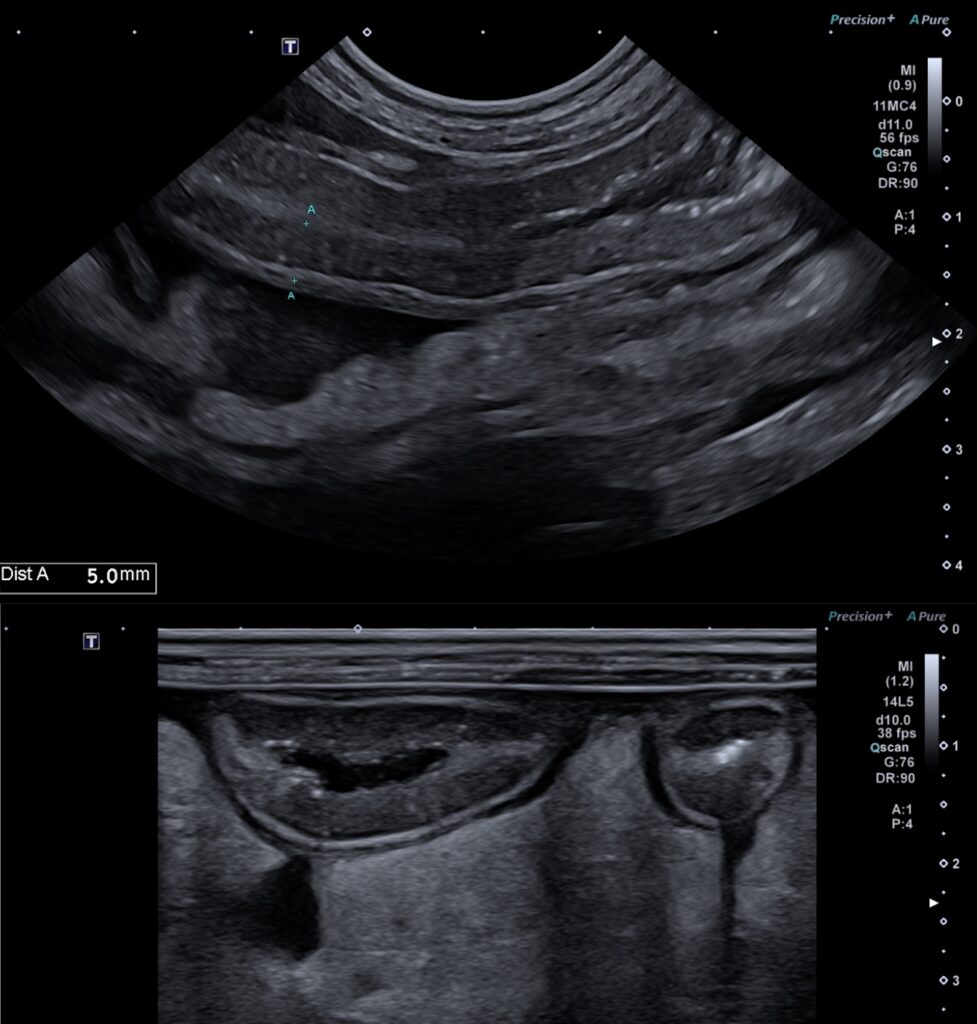

Les lésions muqueuses hyperéchogènes sont typiques d’entéropathie avec perte de protéines chez le chien avec une sensibilité de 76% et une spécificité de 96% dans l’étude de Gaschen et al. Lors de suspicion d’entéropathie chronique chez le chien, la mesure de l’épaisseur seule de l’intestin n’est ni sensible ni spécifique de la présence d’une entéropathie (nombreux faux négatifs). Il convient alors d’apprécier l’aspect de la muqueuse, qui peut présenter soit des « speckles » (= « mouchetures », signe non spécifique ne permettant pas de distinguer le type d’entéropathie), soit des stries hyperéchogènes – figure 1 ci dessous – (corrélé à l’histologie avec une dilatation des glandes lactéales chez le chien, d’après l’étude de Sutherland-Smith et al). Les lymphangiectasies intestinales primitives (ou maladie de Waldmann en médecine humaine), sont caractérisées par des dilatations lymphatiques digestives. Elles entrainent une fuite lymphatique (chyle) dans la lumière intestinale responsable d’une gastro-entéropathie exsudative avec hypoalbuminémie notamment.

Figure 1 : lésions échographiques lors de lymphangiectasie chez un pinscher de 9 ans. Noter l’épaississement pariétal à 5 mm d’une anse jéjunale, la présence de striations et de mouchetures hyperéchogènes dans la couche muqueuse.